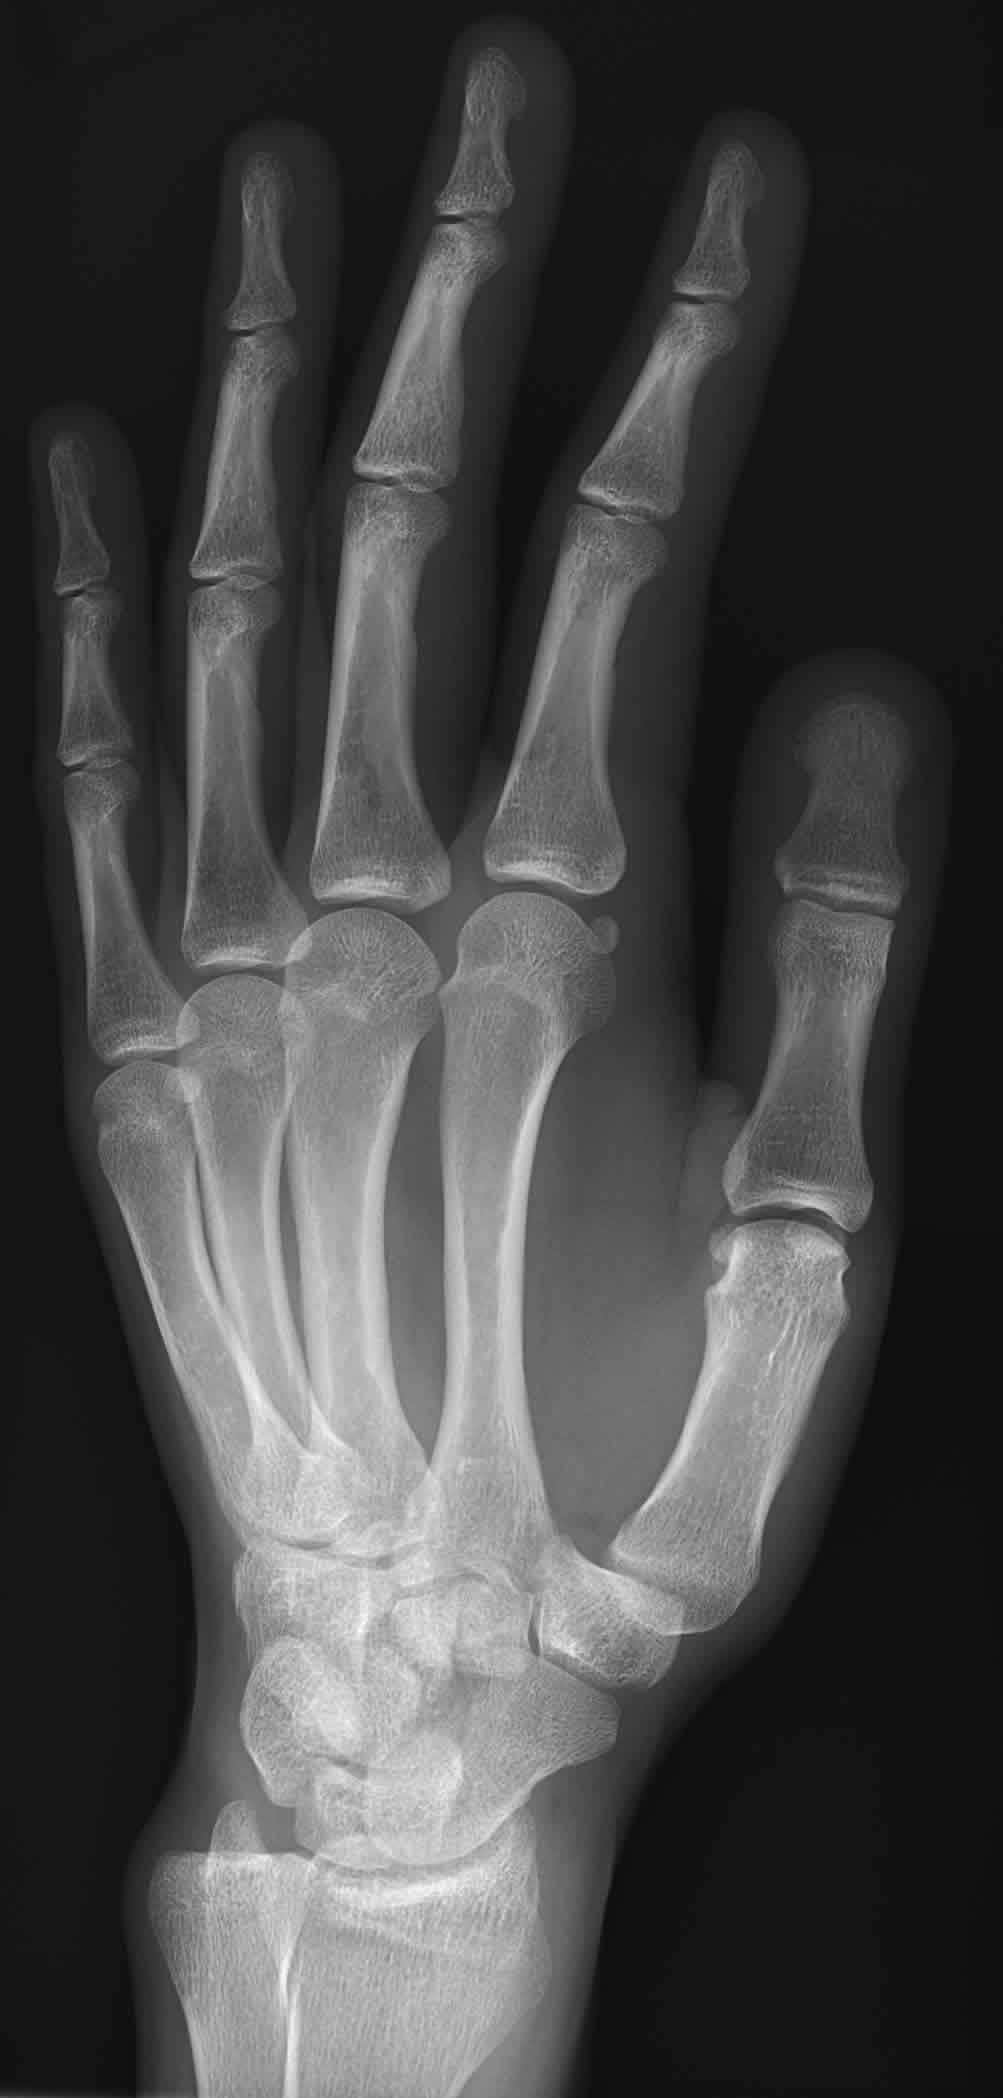

Rayos X Que Es . Los rayos x son ondas electromagnéticas que se usan para obtener imágenes de objetos o cuerpos. Los rayos x son una forma de radiación electromagnética que se usa para hacer imágenes del cuerpo. Descubiertos por el físico alemán rontgen, los rayos x se emplean en medicina, arte y otros campos. Los rayos x son una forma de radiación electromagnética, similar a la luz visible. Los rayos x, o radiografías, son un examen indicado para evaluar posibles alteraciones en los huesos, corazón, pulmones, dientes o columna,. Los rayos x son fotones de alta energía con longitudes de onda cortas que pueden penetrar y ionizar sustancias. Aprenda cómo se realiza el examen,. Los rayos x pasan a través de tu. Fueron descubiertos por wilhelm conrad röntgen en. Sin embargo, a diferencia de la luz, los rayos x tienen mayor energía y pueden atravesar la mayoría. Una radiografía es una prueba rápida e indolora que toma imágenes de las estructuras internas del cuerpo, en especial de los huesos.

Los rayos x, o radiografías, son un examen indicado para evaluar posibles alteraciones en los huesos, corazón, pulmones, dientes o columna,. Los rayos x son ondas electromagnéticas que se usan para obtener imágenes de objetos o cuerpos. Los rayos x pasan a través de tu. Los rayos x son una forma de radiación electromagnética, similar a la luz visible. Los rayos x son una forma de radiación electromagnética que se usa para hacer imágenes del cuerpo. Los rayos x son fotones de alta energía con longitudes de onda cortas que pueden penetrar y ionizar sustancias. Descubiertos por el físico alemán rontgen, los rayos x se emplean en medicina, arte y otros campos. Aprenda cómo se realiza el examen,. Una radiografía es una prueba rápida e indolora que toma imágenes de las estructuras internas del cuerpo, en especial de los huesos. Sin embargo, a diferencia de la luz, los rayos x tienen mayor energía y pueden atravesar la mayoría.

Rayos X Que Es Los rayos x son una forma de radiación electromagnética que se usa para hacer imágenes del cuerpo. Los rayos x son una forma de radiación electromagnética que se usa para hacer imágenes del cuerpo. Los rayos x son fotones de alta energía con longitudes de onda cortas que pueden penetrar y ionizar sustancias. Sin embargo, a diferencia de la luz, los rayos x tienen mayor energía y pueden atravesar la mayoría. Los rayos x son ondas electromagnéticas que se usan para obtener imágenes de objetos o cuerpos. Los rayos x pasan a través de tu. Fueron descubiertos por wilhelm conrad röntgen en. Los rayos x, o radiografías, son un examen indicado para evaluar posibles alteraciones en los huesos, corazón, pulmones, dientes o columna,. Una radiografía es una prueba rápida e indolora que toma imágenes de las estructuras internas del cuerpo, en especial de los huesos. Los rayos x son una forma de radiación electromagnética, similar a la luz visible. Aprenda cómo se realiza el examen,. Descubiertos por el físico alemán rontgen, los rayos x se emplean en medicina, arte y otros campos.